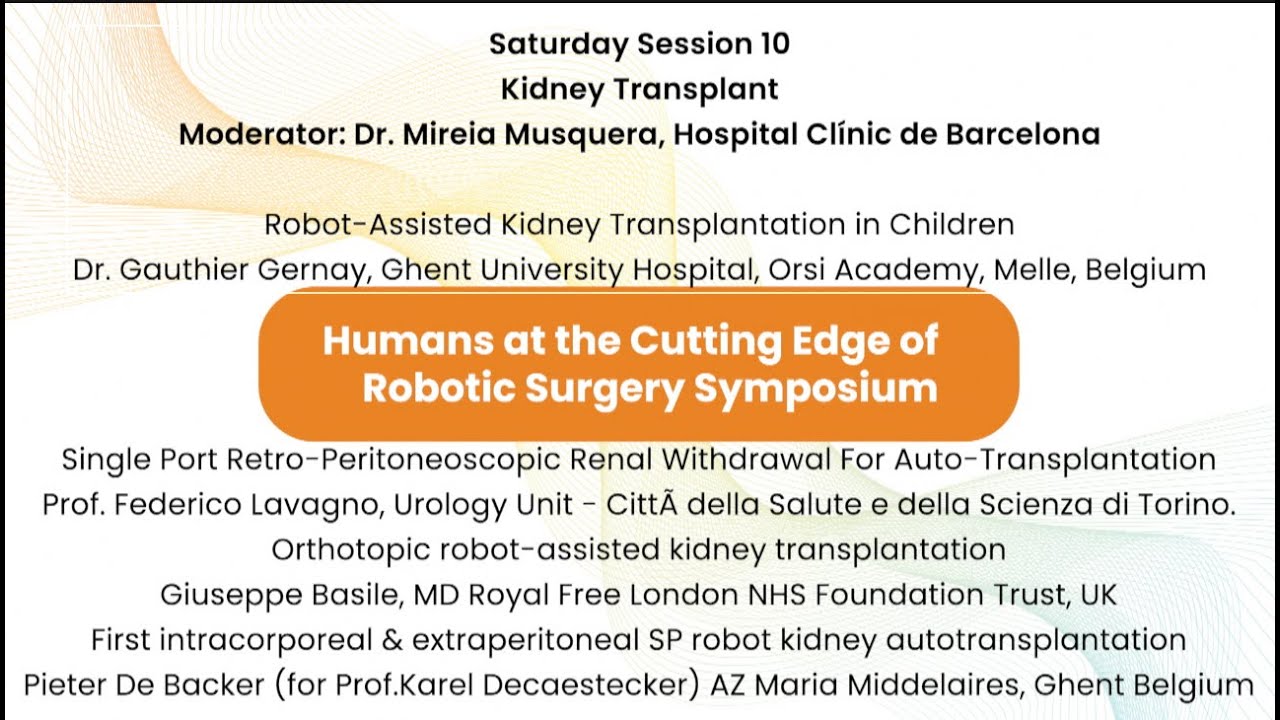

Jaipur Saturday Session 10 Kidney Transplant

Humans of Robotic Surgery, KS Awards, Robotics, Surgeon, Video Library ';